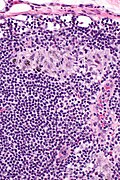

Sinus histiocytosis, abbreviated SH, is a common finding in lymph nodes.

Microscopic

Features:[2]

- Sinuses distended with histiocytes - key feature.

- Plasma cells increased.